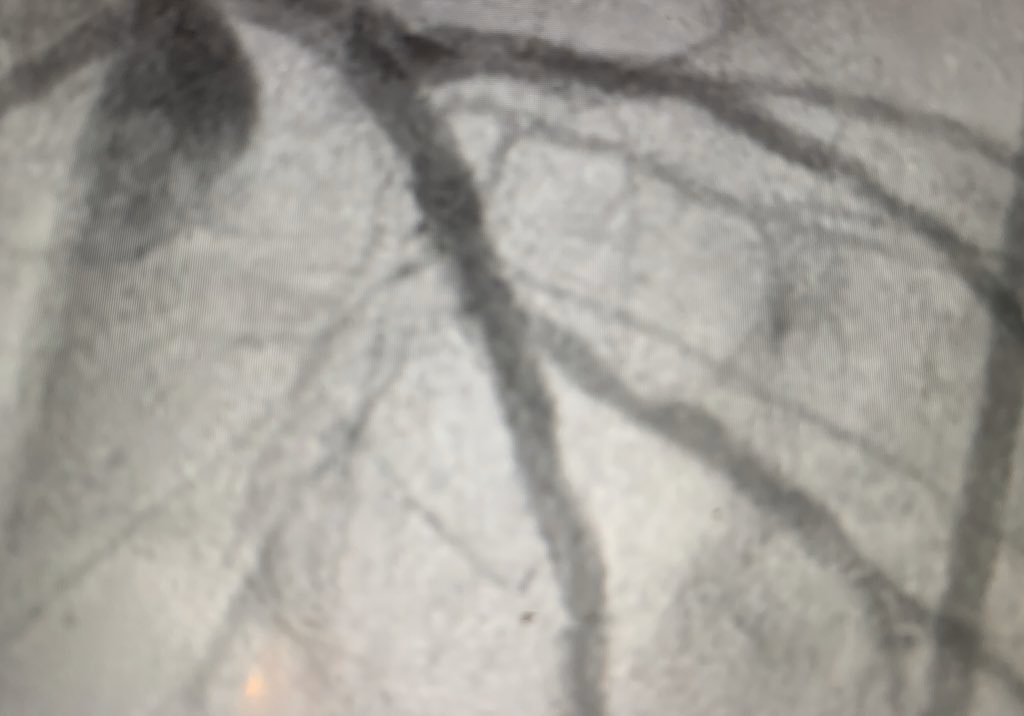

#cardiotwitter#radialfirst How would you treat ?! No IVUS or big stent at this lab. Young 50 female diabetic with recent NSTEMI. I vote for CABG not PCI . pic.twitter.com/gDULYnKcBF -